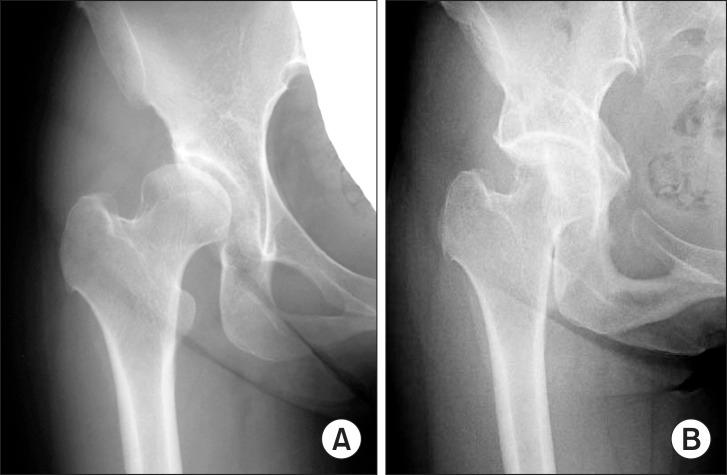

髋臼周围截骨术治疗发育性髋关节发育不良

Curved periacetabular osteotomy (CPO) was developed for the treatment of dysplastic hips in 1995. In CPO, the exposure of osteotomy sites and osteotomy of the ischium are made in the same manner as Bernese periacetabular osteotomy, and iliac and pubic osteotomies are performed in the same manner as rotational acetabular osteotomy. We studied the dynamic instabilities of 25 dysplastic hips before and after CPO using triaxial accelerometry. Overall magnitude of acceleration was significantly decreased from 2.30 ± 0.57 m/sec(2) preoperatively to 1.55 ± 0.31 m/sec(2) postoperatively. Pain relief and improvement of acetabular coverage resulting from acetabular reorientation seem to be related with reduction of dynamic instabilities of dysplastic hips. Isokinetic muscle strengths of 24 hips in 22 patients were measured preoperatively and after CPO. At 12 months postoperatively, the mean muscle strength exceeded the preoperative values. These results seem to be obtained due to no dissection of abductor muscles in CPO. The preoperative presence of acetabular cysts did not influence the results of CPO. An adequate rotation of the acetabular fragment induced cyst remodeling. Satisfactory results were obtained clinically and radiographically after CPO in patients aged 50 years or older. CPO alone for the treatment of severe dysplastic hips classified as subluxated hips of Severin group IV-b with preoperative CE angles of up to -20° could restore the acetabular coverage, weight-bearing area and medialization of the hip joint. CPO without any other combined procedure, as a treatment for 17 hips in 16 patients with Perthes-like deformities, produced good mid-term clinical and radiographic results. We have been performing CPO in conjunction with osteochondroplasty for the treatment of acatabular dysplasia associated with femoroacetabular impingement since 2006. The combined procedure has been providing effective correction of both acetabular dysplasia and associated femoral head-neck deformities without any increased complication rate. We have encountered an obturator artery injury in one case and two intraoperative comminuted fractures. Although serious complications such as motor nerve palsy, deep infection, necrosis of the femoral head or acetabulum, and delayed union or nonunion of the ilium were reported, such complications have never occurred in our 700 cases so far.

髋臼周围截骨术(CPO)于1995年被开发用于治疗发育性髋关节发育不良。在CPO中,截骨部位的暴露和坐骨截骨的方式与伯尔尼髋臼周围截骨术相同,髂骨和耻骨截骨的方式与旋转髋臼截骨术相同。我们使用三轴加速度计研究了25例发育性髋关节发育不良患者在CPO前后的动态不稳定性。总体加速度大小从术前的2.30±0.57米/秒²显著降低至术后的1.55±0.31米/秒²。髋臼重新定位带来的疼痛缓解和髋臼覆盖改善似乎与发育性髋关节动态不稳定性的降低有关。对22例患者的24个髋关节在术前和CPO后进行了等速肌力测量。术后12个月时,平均肌力超过了术前值。这些结果似乎是由于CPO中未对外展肌进行剥离而获得的。术前髋臼囊肿的存在并未影响CPO的结果。髋臼碎片的适当旋转导致囊肿重塑。50岁及以上患者在CPO后在临床和影像学上均获得了满意的结果。单独使用CPO治疗术前CE角高达-20°的Severin IV-b组半脱位型严重发育性髋关节发育不良,可恢复髋臼覆盖、负重面积和髋关节内移。对于16例佩特兹样畸形患者的17个髋关节,在未进行任何其他联合手术的情况下进行CPO,取得了良好的中期临床和影像学结果。自2006年以来,我们一直将CPO与骨软骨成形术联合用于治疗与股骨髋臼撞击相关的髋臼发育不良。该联合手术在不增加并发症发生率的情况下有效矫正了髋臼发育不良和相关的股骨头颈畸形。我们遇到过1例闭孔动脉损伤和2例术中粉碎性骨折。虽然有报道称出现过诸如运动神经麻痹、深部感染、股骨头或髋臼坏死以及髂骨延迟愈合或不愈合等严重并发症,但在我们目前的700例病例中从未发生过此类并发症。